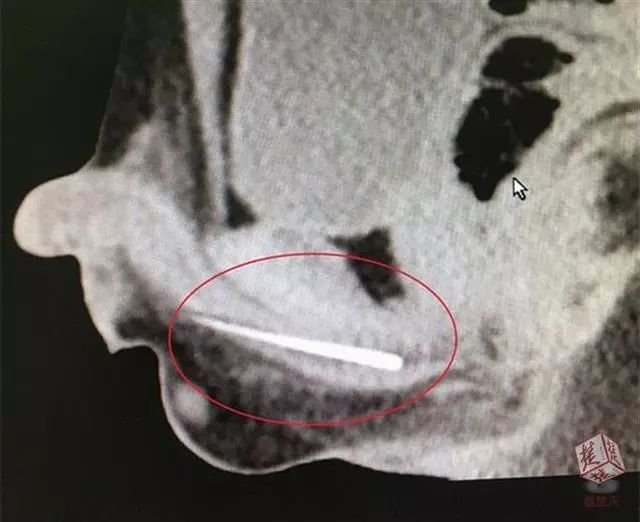

于是,鹏鹏找来妈妈的绣花针,针长约6厘米,然后他在磊磊的指导下慢慢把放进尿道。此时恰好妈妈推门进来找东西,鹏鹏一慌,把针全塞了进去,并迅速穿好衣服。

绣花针终于取出来了!